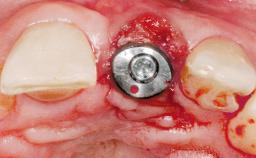

Late Placement of an Implant in a Maxillary Left Central Incisor Site

A 30-year-old female patient had lost tooth 21 and was referred to our clinic for consultation and treatment. Due to advanced apical infection, tooth 21 had been extracted two months earlier at another clinic and an acrylic-resin tooth had been bonded to the adjacent teeth. The patient desired implant treatment to avoid any damage to the adjacent natural teeth. While the patient had no history of any systemic disorder, she was a heavy smoker and exhibited medium to advanced periodontitis in the entire jaw. After the initial treatment to achieve a pocket probing depth of less than 4 mm and no bleeding on probing, a decrease in the height of the papillae mesial and distal to the extraction site and overall gingival recession were observed.

Type of Implants One-Piece|Reduced-Diameter

Bone Augmentation Horizontal|Staged

Soft Tissue Grafting Simultaneous